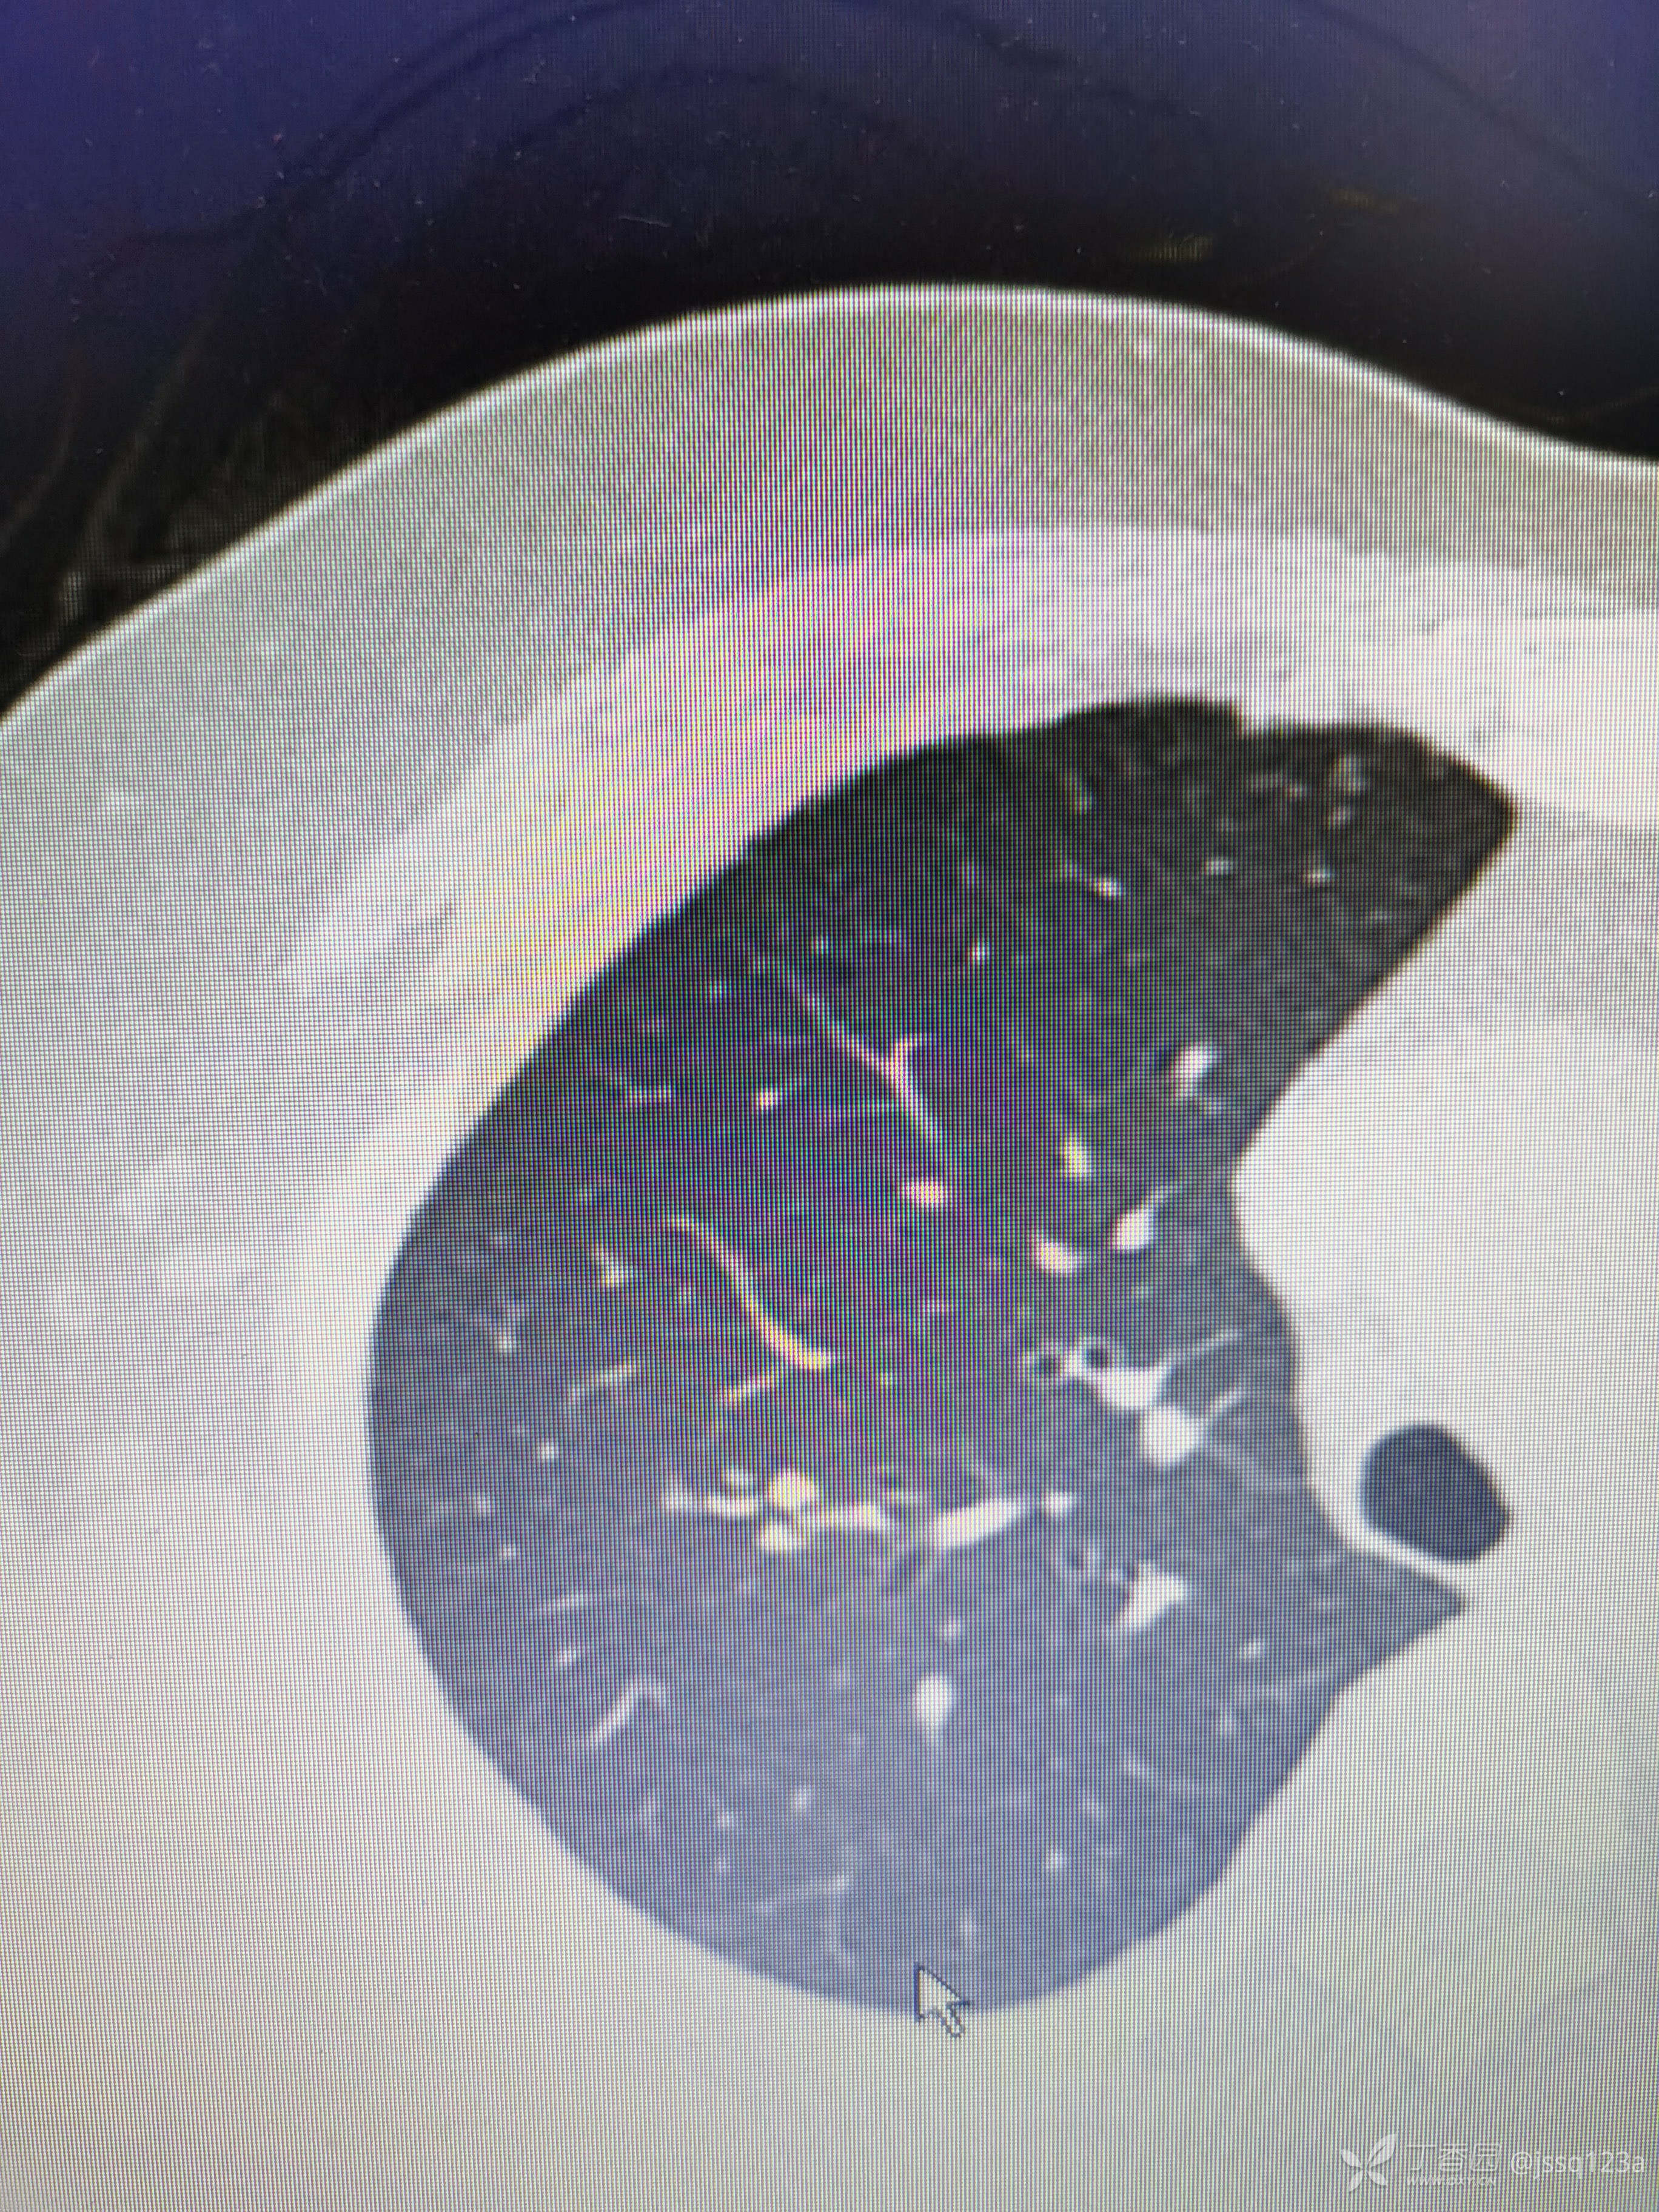

复查胸部ct

病史:患者女,59岁,自诉半年前受凉后反复咳嗽咳痰,期间头孢输液三天后症状好转,其后偶有咳嗽,无畏寒发热,咯血胸闷,夜间盗汗。2021-11-29查胸部ct:右肺上叶多发异常密度影,考虑感染。怀疑结核可能,入院后查血常规正常。痰检三次阴性,支气管灌洗液涂片阴性,培养阴性。支气管镜检查见左侧支气管及各侧支气管均有较多痰栓附着,较难吸出。结核T-SPOT阳性。予以美洛西林+乳酸左氧氟沙星抗感染治疗10天,复查胸部ct病灶未见明显吸收。胸部ct2021-12-10示:右肺上叶及中叶多发高密度影。